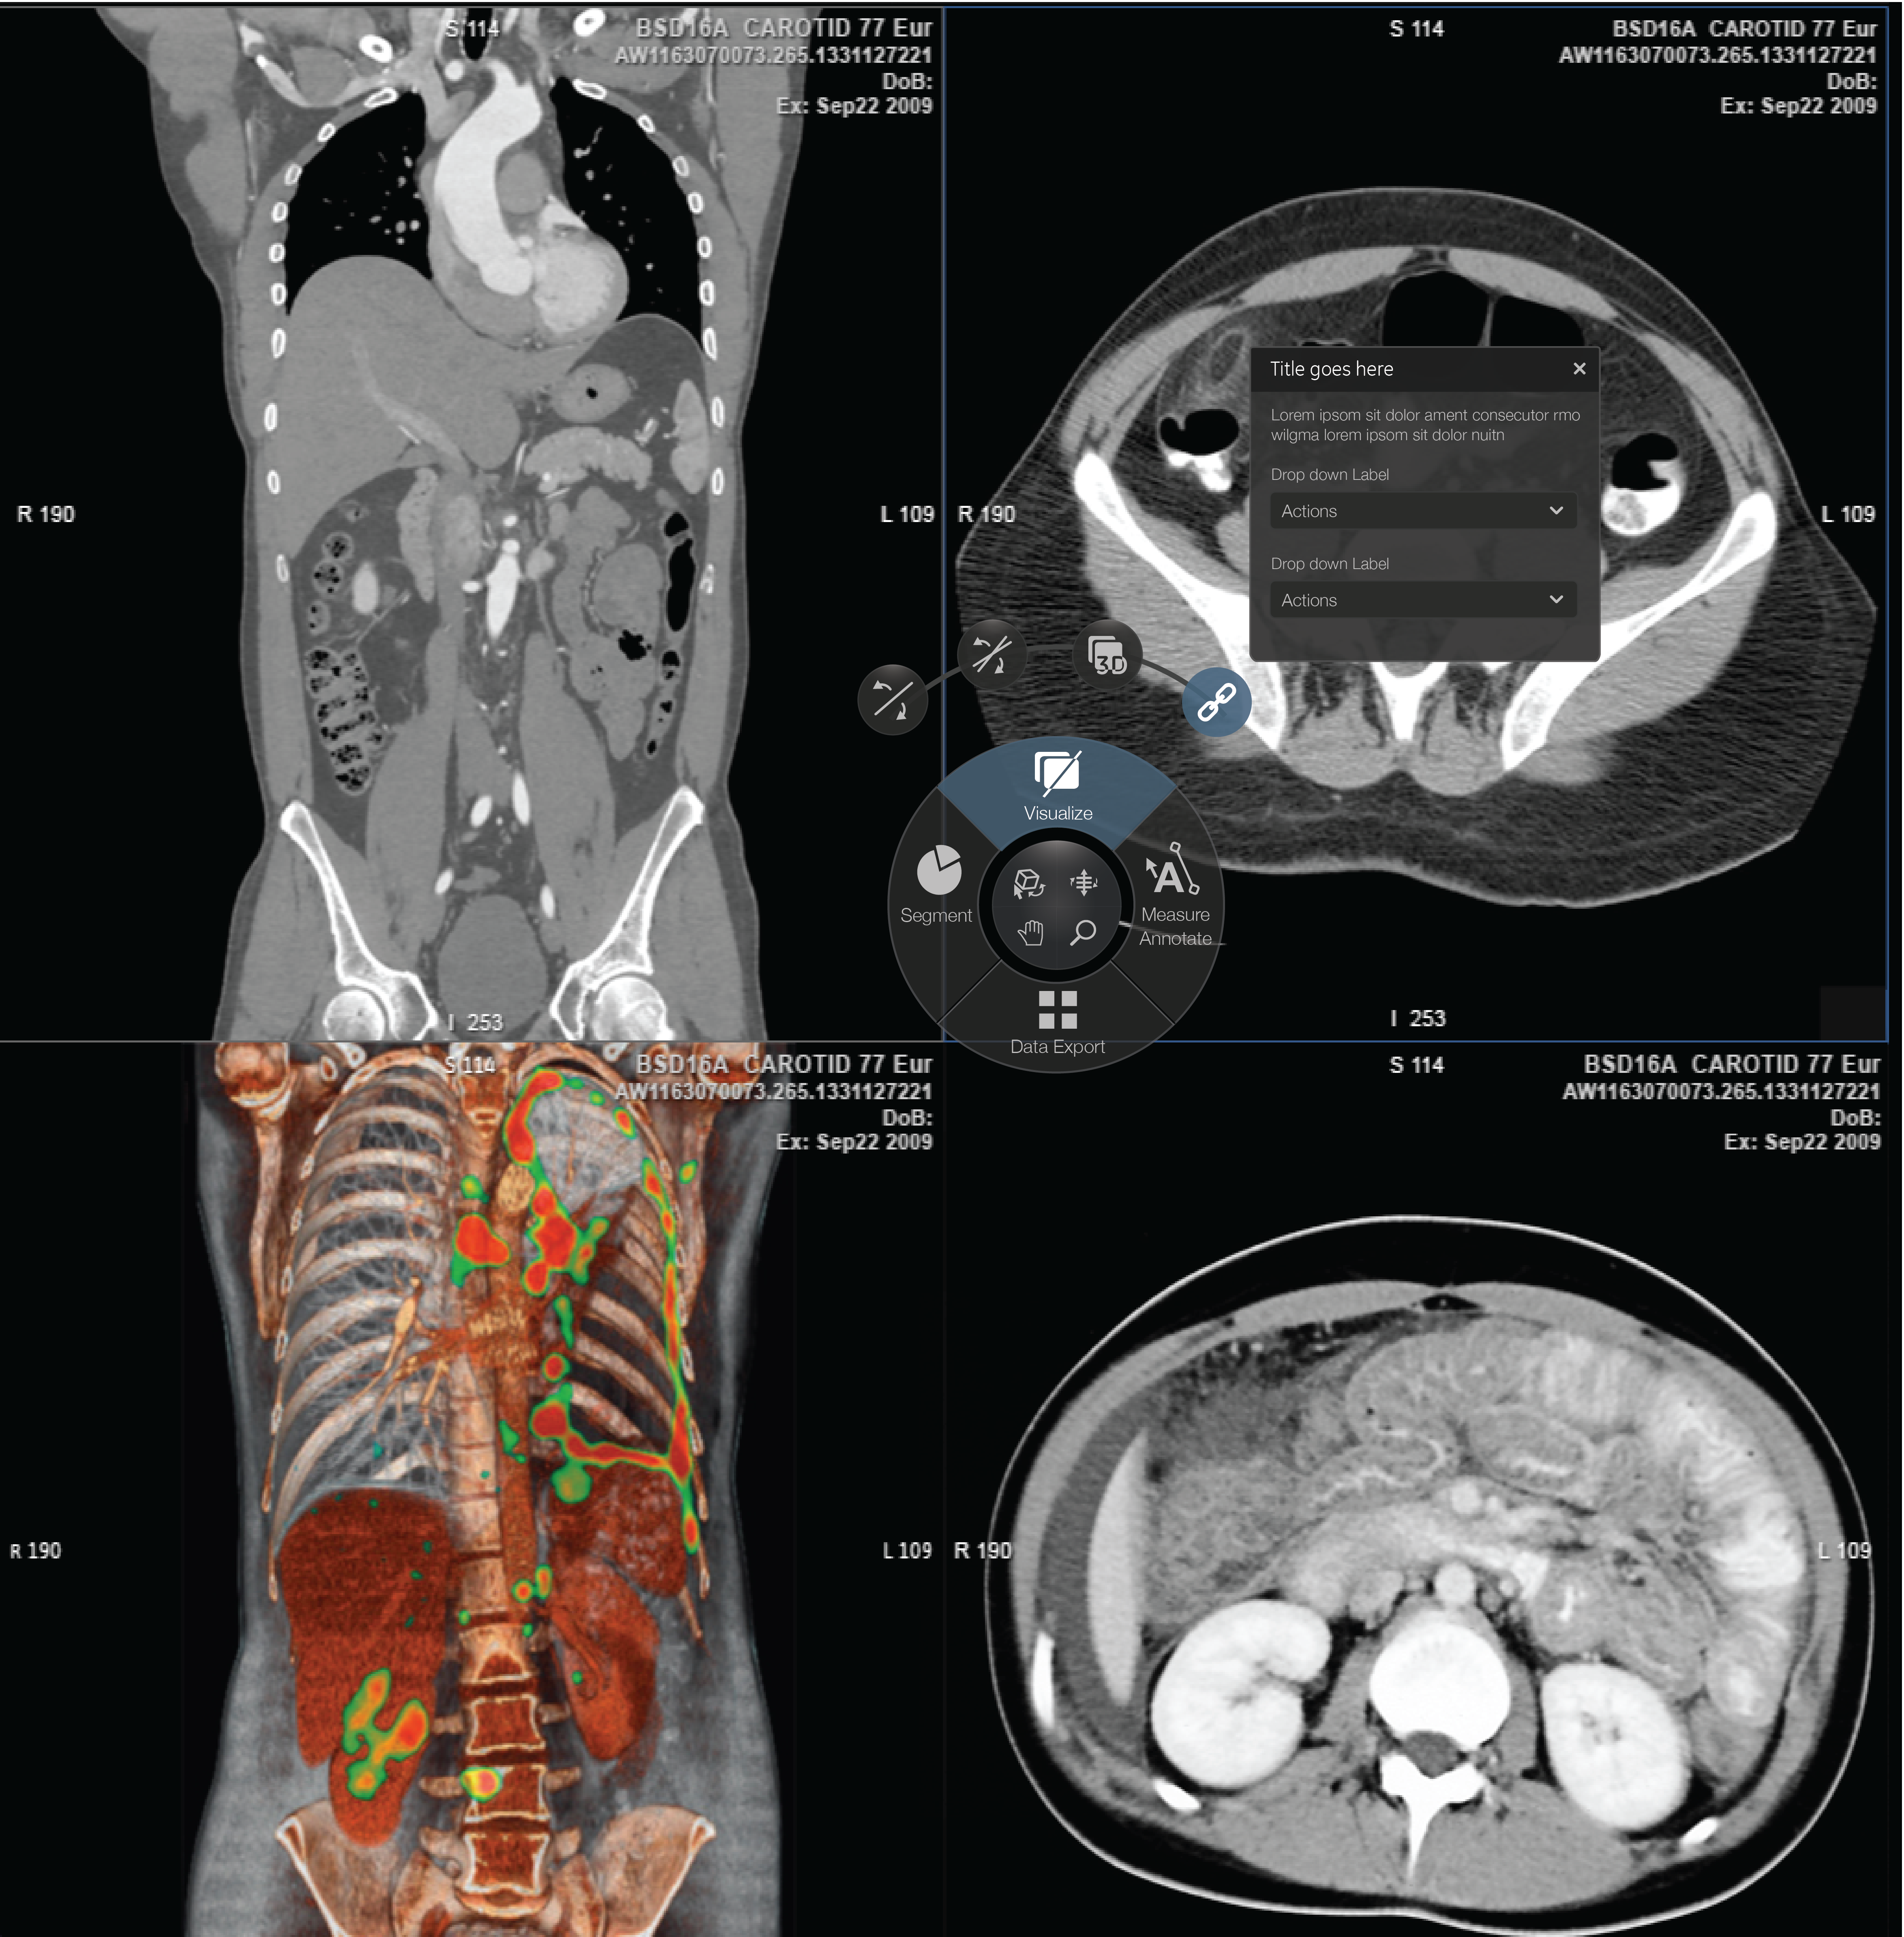

Radial menu component: Interaction and visual design for a GE Healthcare. Allowing Radiology Tehnicians a quick-access menu to access high-use tools within this menu anywhere on their monitors.

Final Composition